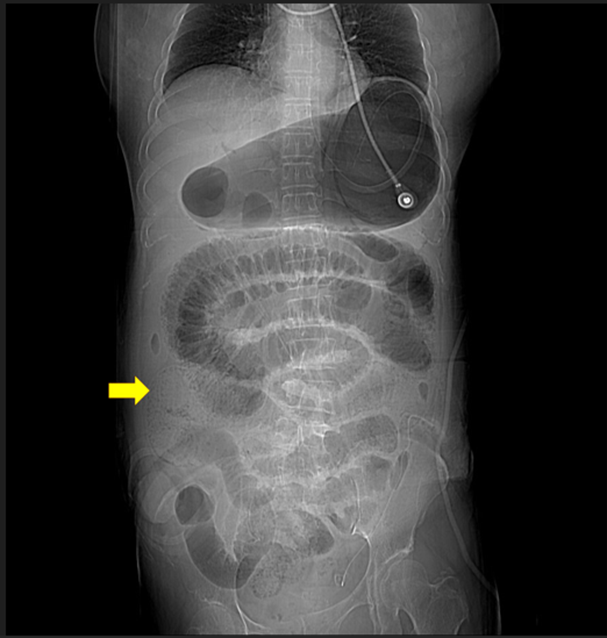

A female aged 48 years underwent neoadjuvant radiotherapy for the rectal adenocarcinoma preoperatively and low anterior resection for the tumor one month afterward after complete radiotherapy. Because of the very low colonic anastomosis and the previous radiotherapy, the ileostomy coincided for fecal diversion. Primarily, her postoperative recovery was smooth. After her oral intake without any discomfort, she was discharged after post-op day 7. Withal, she returned to our hospital due to persistent vomiting, progressive abdominal pain and abdominal bloating after she discharged 2 days afterwards. Physical examination averred abdominal bloating and hypoactive bowel sound but no peritoneal sign. Notwithstanding the severely edematous ileostomy, no gangrene change existed; sepsis, leukocytosis (WBC: 19400/mL), metabolic acidosis, and elevated lactate levels (7.5 mmole/L) were evinced. The abdominal computed tomography (CT) from the stomach to the small bowel denoted diffuse dilatation (Figure 1) and pneumatosis intestinalis (PI) and portal venous gas (PVG) (Figure 2, 3). Owing to these symptoms, she was admitted in our intensive care unit for advance treatment. Non-operative treatment because there was no peritoneal sign and the ileostomy was still in good appearance. Those treatments covering nasogastric tube (NG) for gastrointestinal (GI) tract decompression, large amount fluid supply (3000ml/day) and antibiotics (ceftriaxone 1gm Q12H and metronidazole 500mg Q8H) was for her sepsis status. Her abdomen and ileostomy conditions scrutinized could be contributed to emergent operations if getting worse. The edematous ileostomy started to improve two days subsequently. The ileostomy-made flatus and stool passage were on readmission day 5. The oral liquid diet ingestion began; the transfer to the general ward was on re-admission day 7. Attributed to no abnormal abdominal lesion, the soft diet was applied. Eventually, she was discharged on re-admission day 12. Till present, no other abdominal lesion was identified in out-patient department follow up.

Figure 1: Diffuse dilatation from stomach to small bowel, the dilation of bowel end at ileostomy (arrow)